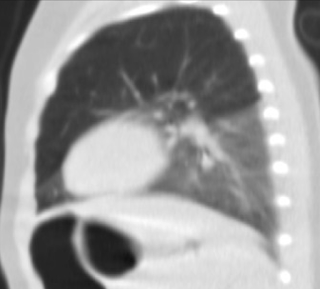

Escanografía